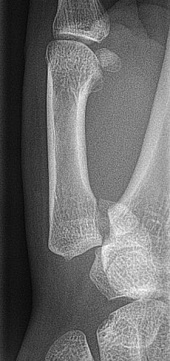

A patient presents to A+E with a sore wrist. Since the injury, they state that they are unable to grab things and the pain is greatest over the base of the thumb.

a) i) telescoping of thumb elicits pain, ii) point of maxminal tenderness over snuffbox and iii) Tenderness over back of wrist

b) Scaphoid fracture

c)

i) AP and Lateral X rays

ii) MRI scan